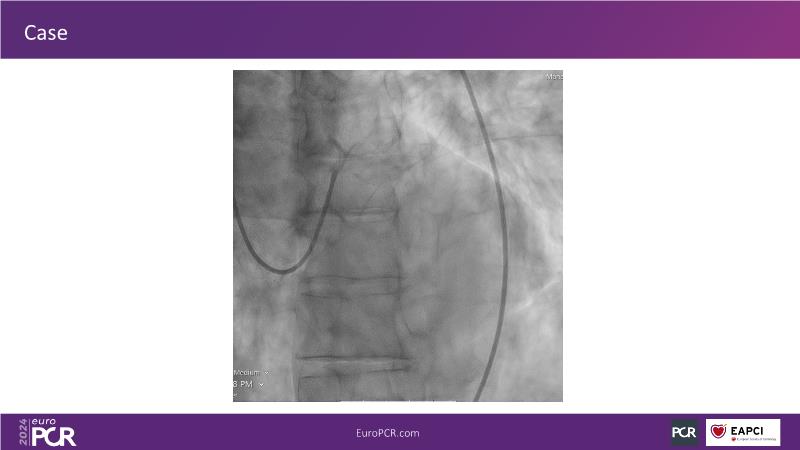

Tune into this 2024 session for insights into the latest ESC guidelines, strategies to prevent and treat no reflow, and an examination of trials like TASTE, TAPAS, and TOTAL on coronary thrombus management. Explore also the outcomes of the CHEETAH study, pondering a potential paradigm shift, and delve into a case study on thrombus removal in a patient with high thrombus burden.